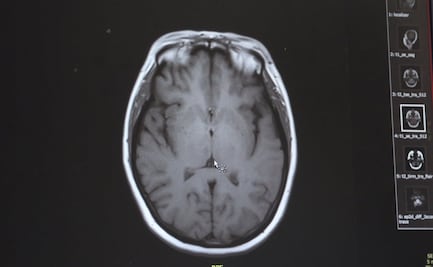

Vive en la tierra y en aguas cálidas de todo el mundo; entra al cuerpo humano por inhalación y de ahí se desplaza al cerebro

Tras más de 15 días de su infección, se dio a conocer que el menor, de quién no se conoce su identidad, falleció por la ameba comecerebros, que según autoridades, pudo contraer en un parque público

El estado se encuentra en alerta desde el pasado 8 de septiembre, cuando justo en Lake Jackson se dio a conocer el caso de un niño de seis años quien fue hospitalizado por la ameba, sin embargo falleció